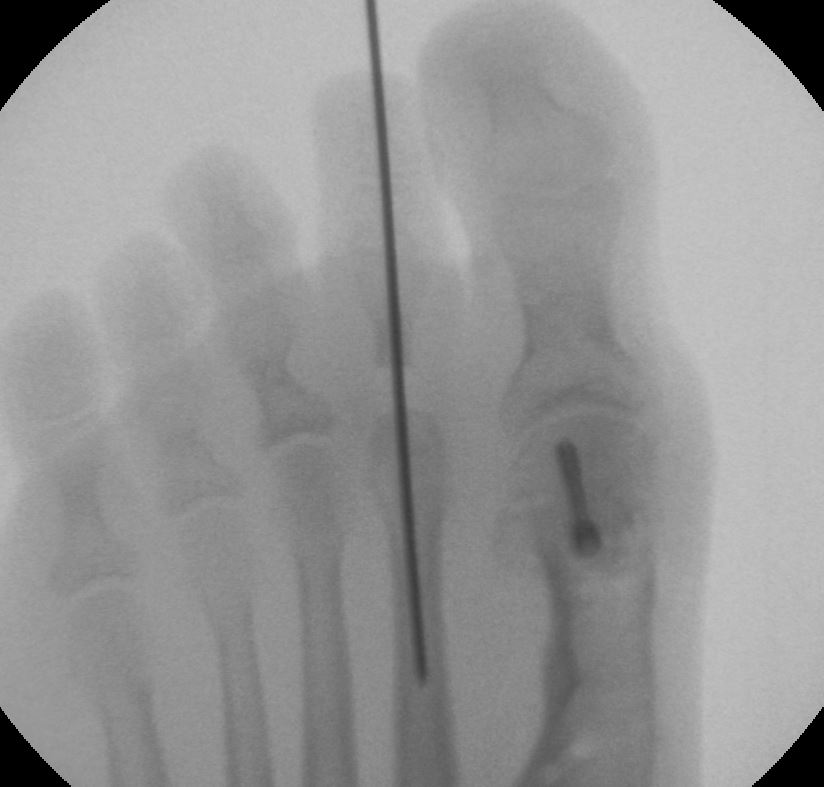

Röntgebild aus dem OP von Dr. Böhr in der Klinik Sanssouci: Stainsby OP am zweiten Zeh bei kontrakter Krallenzehe und Hallux Valgus